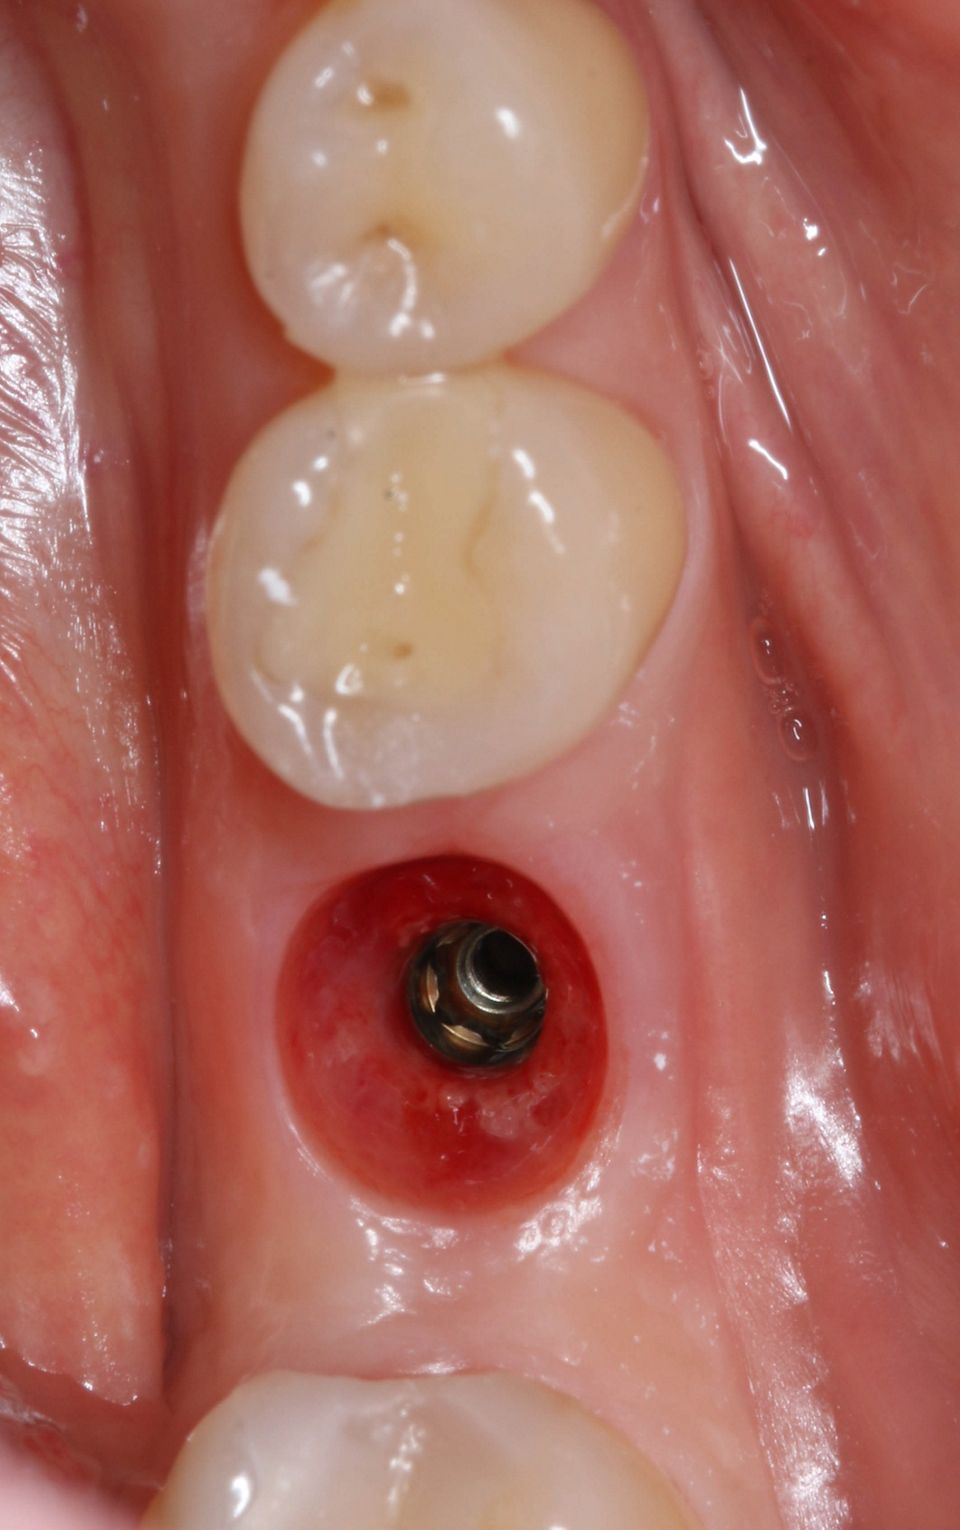

手术后一周,拆线(图11-12)。在同一次就诊时,拍摄了垂直牙科射线照片(图 13),显示种植体处于正确的修复位置。四个月后,愈合基台被移除。粘膜外观表明植入物周围有稳定且健康的软组织,具有足够的生物宽度和光滑的出现轮廓(图14-15)。取印模,一个月后,将最终的氧化锆陶瓷牙冠拧到种植体上(图 16-18)。